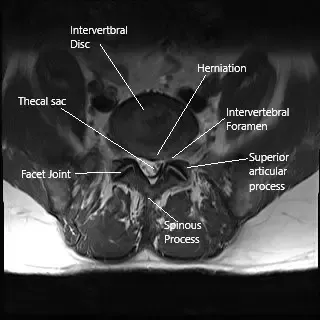

MRI axial section of the lumbar spine showing foraminal stenosis.

MRI of the lower spine revealed an L4-L5 diffuse disc bulge with superimposed right central

subarticular and foraminal disc protrusion (disc herniation) and intermediate-grade central canal and high-grade foraminal stenosis, right greater than left. There is an L5-S1 shallow left central and subarticular disc protrusion (disc herniation).